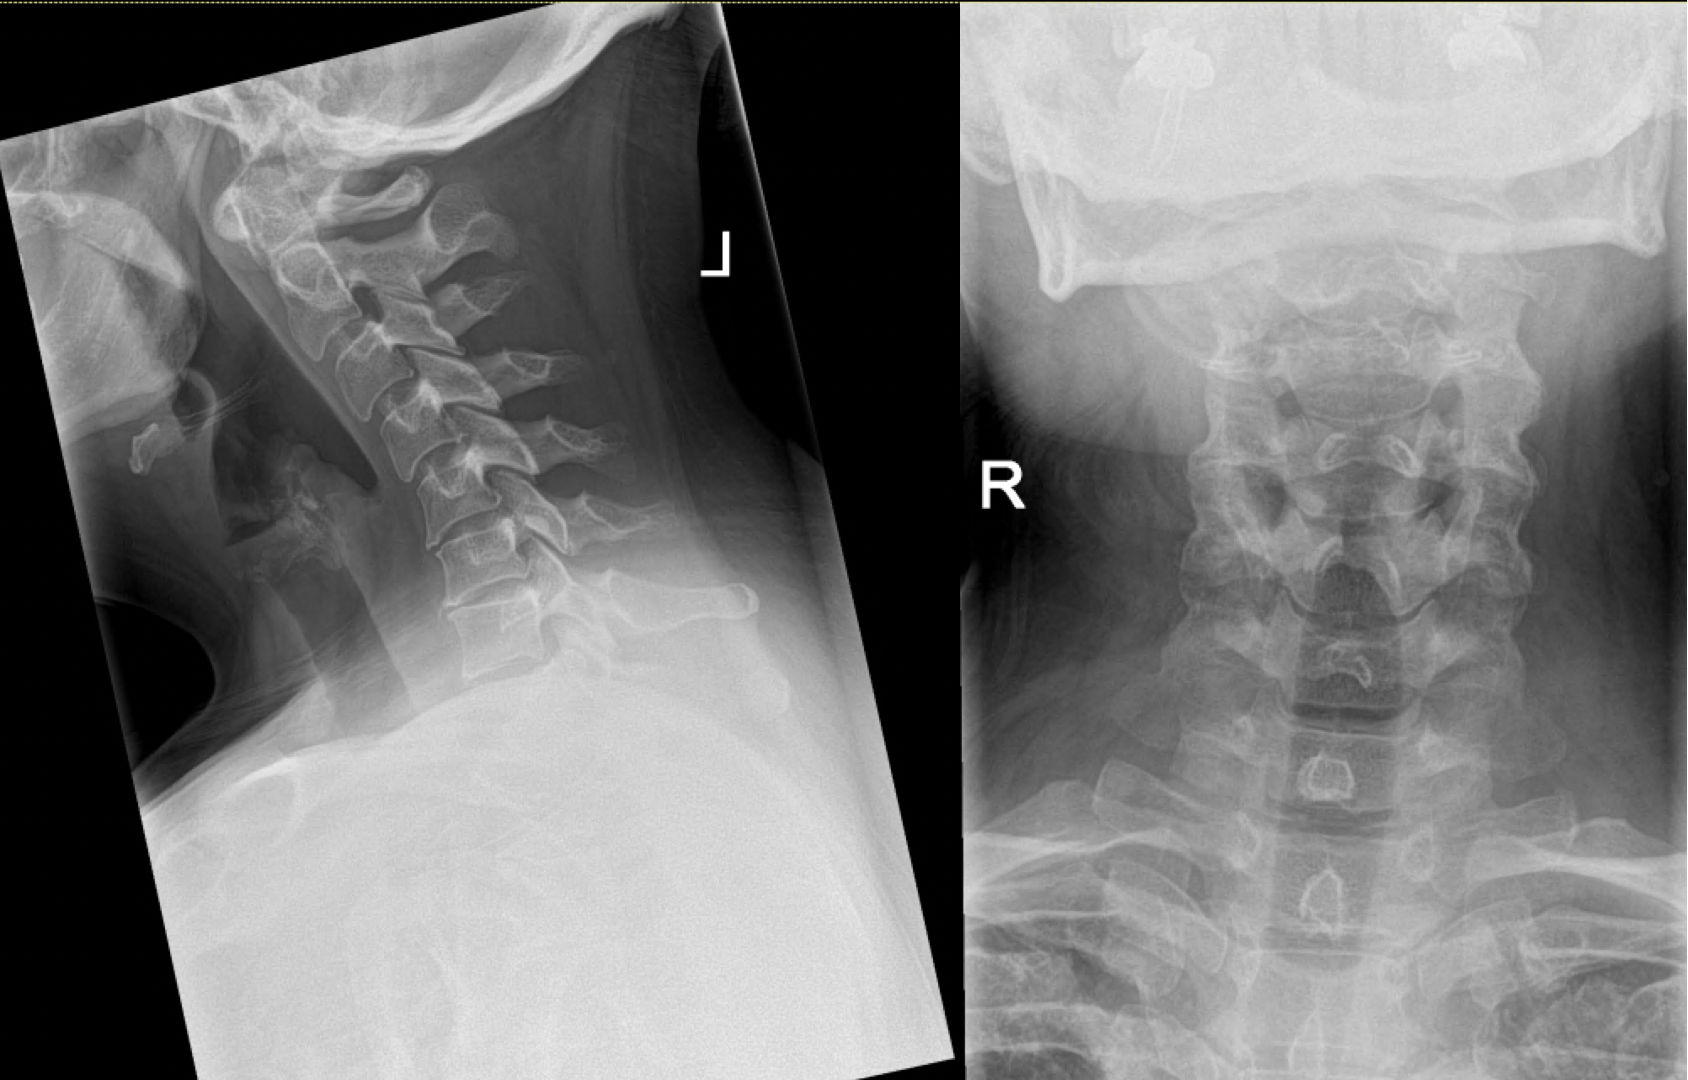

Diagnosis and Investigations

The diagnosis of cervical radiculopathy and myelopathy is usually made clinically based on history and examination. It is then confirmed with radiological imaging tests most notably an MRI scan. Other imaging tests, such as X-ray and CT are sometimes appropriate. Occasionally, electromyography (EMG) or nerve conduction study (NCS) are required.